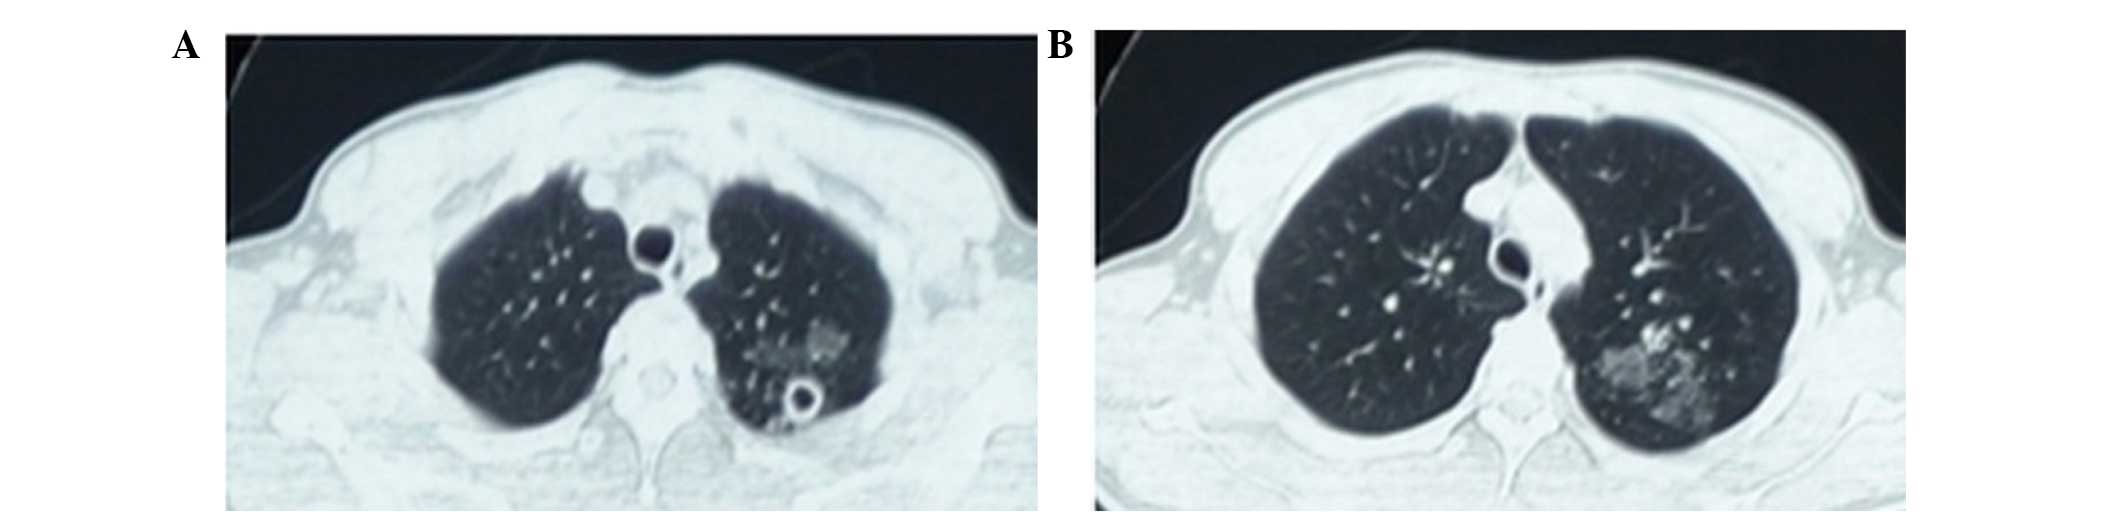

Upon presentation, the patient's vital signs were normal: Body temperature, 37.2°C; heart rate, 72 beats/min; respiratory rate, 17 breaths/min; blood pressure, 115/70 mm Hg; and oxygen saturation in room air, 99%. However, auscultation revealed crackles in the left upper lung fields. The patient's heart rate was regular and heart sounds were normal, with no murmurs, clicks, gallops or rubs. Thoracic computed tomography (CT) was performed using a GE LightSpeed VCT 64 slice CT scanner (GE Healthcare Bio-Sciences, Pittsburgh, PA, USA) and detected small round thick-walled cavities in the apex of the left lung and multiple patchy ground-glass opacities in the left upper lobe of lung (Fig. 1).

Figure 1.

Findings of thoracic computed tomography scanning in April 2014. (A) Small round thick-walled cavities were observed in the apex of the left lung and (B) multiple patchy ground-glass opacities were detected in the left upper lobe of the lung.